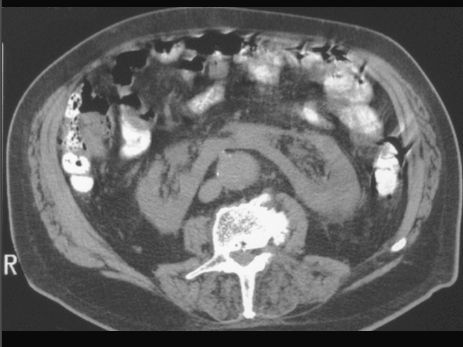

NERKA PODKOWIASTA

TK